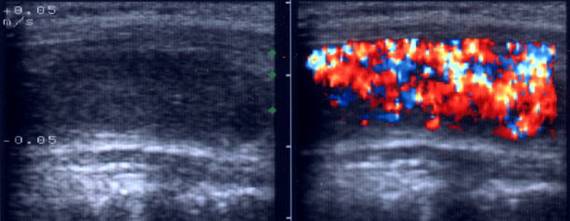

Acelasi pacient. La doppler color, vascularizatie bogata, difuza in toata

glanda

Artera tiroidiana superioara stg.

Artera tiroidiana superioara dreapta.

Acelasi

pacient. La doppler color, vascularizatie bogata, difuza in toata glanda